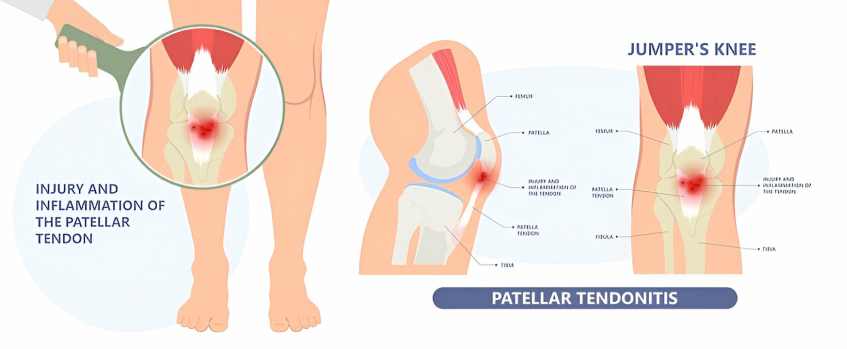

Patellar tendonitis is a common injury or inflammation of the tendon that connects your kneecap (patella) to your shinbone (tibia). Your pain may be mild or severe.

Anyone can get patellar tendonitis. But it’s such a frequent injury of athletes, especially those who play volleyball and basketball, that it’s called jumper’s knee.

Patellar tendonitis comes from repetitive stress on the knee, most often from overuse in sports or exercise. The repetitive stress on the knee creates tiny tears in the tendon that, over time, inflame and weaken the tendon.

Athletes are more at risk because running, jumping, and squatting put more force on the patellar tendon. For example, running can put a force of up to five times your body weight on your knees.

Pain and tenderness at the base of your kneecap are usually the first symptoms of patellar tendonitis. You may also have some swelling and a burning feeling in the kneecap. Kneeling down or getting up from a squat can be especially painful.

The pain may at first be sporadic, occurring only after sports or exercise activity. As the tendon becomes more damaged, the pain can become progressively worse. It can interfere with any athletic activity, as well as with daily activities, such as climbing stairs or sitting in a car.